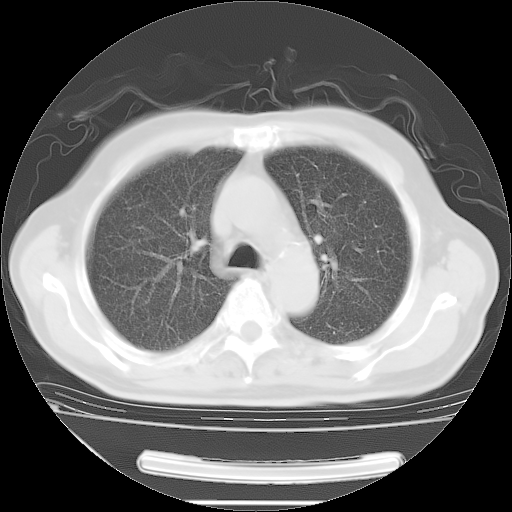

今天复查肺部CT,发现双肺广泛磨玻璃样改变。所以我把3月19日和5月9日相隔50天的肺部CT上传。请大家会诊。

2009年3月19日肺部CT片。

2009年3月19日肺部CT

大致读了系列胸部CT:纵隔窗无明显异常,肺窗:从4、27至今:主要是双肺中下野外带可见毛玻璃样改变,目前处于急性肺泡炎阶段,至于原因考虑1、结替组织或胶原血管性疾病所致?2、恶性疾病如恶组在肺部所致的表现或细支气管肺泡癌?3、药物或其它原因如肺蛋白沉着症所致肺泡炎目前不太可能?总之,明天就去请我院的呼吸科、感染科、血液科和临免专家会诊哈。